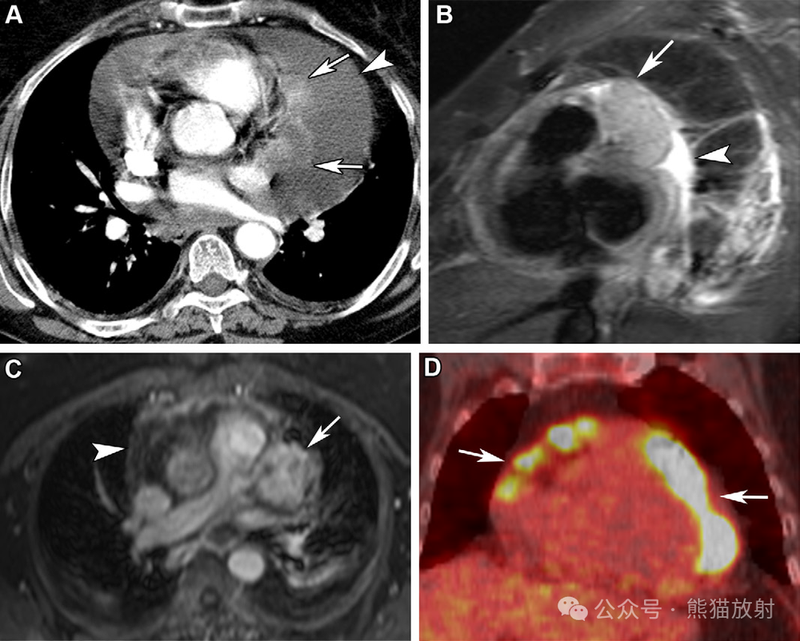

68岁女性,心包间皮瘤。(A) 增强胸部 CT 图像显示心包结节样增厚(箭)和大量心包积液(箭头)。(B,C) 矢状位T2WI (B) 和轴位对比增强T1WI (C) MR 图像显示有强化的T2等信号心包肿块(箭)和心包积液(箭头)。(D) 冠状18F-FDG PET/CT 图像显示明显高代谢的心包肿块 (箭头)。